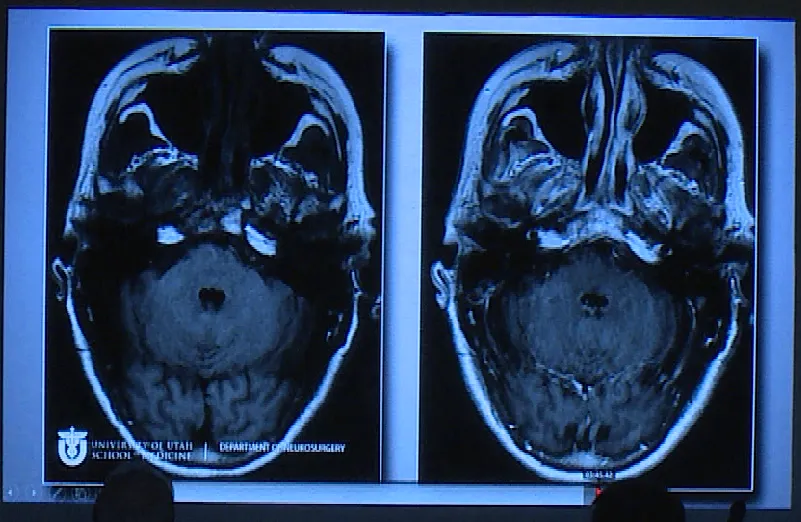

一位62岁女性患者,与垂体瘤抗争已达35年,曾因垂体瘤复发接受放射治疗。本次因复视症状随访检查,发现已发展为巨大垂体瘤。实施开颅手术后,术后影像显示肿瘤切除彻底。

Couldwell教授演讲中展示部分巨大垂体瘤病例。目前巨大垂体瘤主要治疗方式为手术,目的在于最大程度切除肿瘤、改善神经功能障碍以及保留正常垂体功能。巨大垂体腺瘤术前根据影像学表现和临床症状,个体化选择合适手术入路,是成功切除肿瘤的关键。经蝶入路、经颅入路和联合入路是切除肿瘤的可行方法。